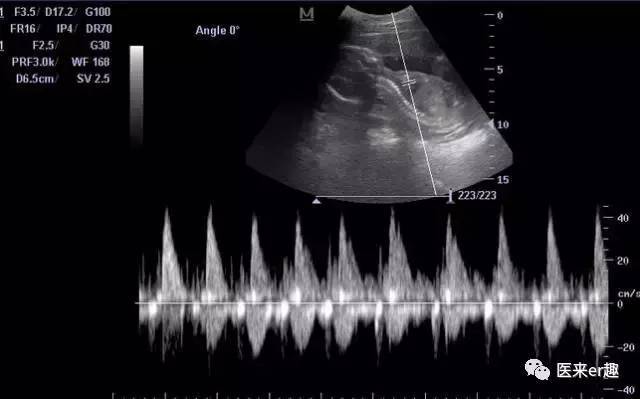

胎儿心脏超声强回声(EIF,echogenic intracardiac focus)现象最早于1987年被报道,目前发生率大约是2%~5%。

大部分学者认为,EIF是一种超声声像图而不是心脏畸形,对心脏的发育及血液动力学无明显影响。强回声结构可能是增厚的腱索、乳头肌或异位肌束,或多条腱索聚集产生较强的反射所致。也可能是由于乳头肌的微小钙化多引起的声学改变等等,而上述心内微结构的改变并无碍健康和心脏功能。

强回声光点或光斑,直径一般1-6mm不等,常单发,也可为多发,90%出现在左室,也可见于右心室,或左右心室同时存在。单纯出现左心室强回声一般不用担心,大约95%会在孕晚期消失。